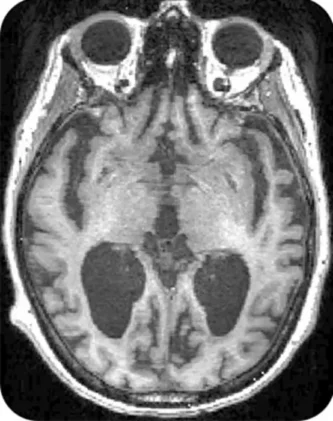

The AI system, trained on brain scans, genetic data, and amyloid measurements, split the 1,354 trial participants into two groups: those progressing slowly toward full-blown Alzheimer’s and those declining rapidly. While the drug failed to slow cognitive decline in fast progressers, it proved remarkably effective in the slow-progressing group.

The AI model proved three times more accurate than standard clinical assessments based on memory tests, MRI scans, and blood tests in predicting disease progression. It analyzes the complex relationships between brain imaging, genetic factors, and protein levels to generate individual patient prognosis scores.